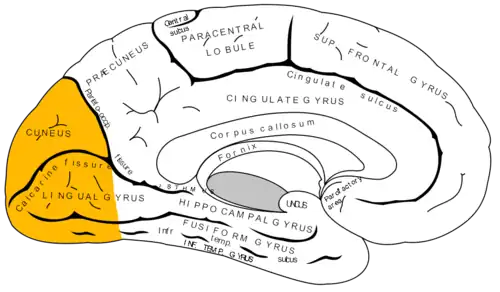

Lóbulo occipital

El lóbulo occipital es uno de los seis lóbulos principales,[1][2][3] de cada hemisferio del cerebro.

El lóbulo occipital da forma a la parte posterior de cada hemisferio cerebral llamada polo occipital y no está claramente separado mediante surcos de los lóbulos parietal y temporal.[6]

El lóbulo occipital muestra una forma piramidal con vértice posterior en el polo occipital. Su cara lateral externa es convexa, su cara interna o medial es plana y su cara inferior es ligeramente cóncava.

La cisura calcarina, situada en la cara medial, atraviesa la superficie interna del lóbulo por su parte media, extendiéndose desde la extremidad posterior del polo occipital, hasta la cisura parieto-occipital.[7]